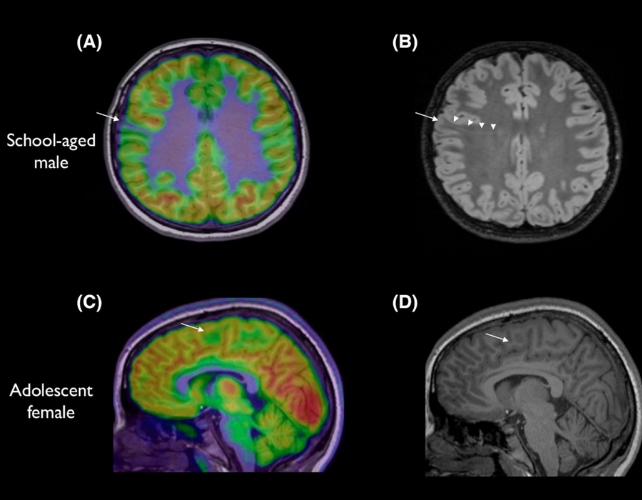

| Hình ảnh chụp não của 2 bệnh nhân với các tổn thương não không được phát hiện trong lần chụp MRI đầu tiên. |

Kết quả thử nghiệm cho thấy công cụ đạt hiệu quả vượt trội. Ở nhóm bệnh nhân loạn sản vỏ não và động kinh cục bộ, trong khi 80% từng có kết quả MRI bình thường thì AI đã phát hiện tổn thương với độ chính xác 94% ở một nhóm và 91% ở nhóm khác, khi kết hợp phân tích cả MRI và PET.

Trong số 17 trẻ thuộc nhóm đầu tiên, 12 em được phẫu thuật loại bỏ tổn thương. Kết quả, 11 em đã thoát khỏi các cơn động kinh. Hiện nay, động kinh ảnh hưởng đến khoảng 1/200 trẻ em và một phần ba trong số này kháng thuốc.